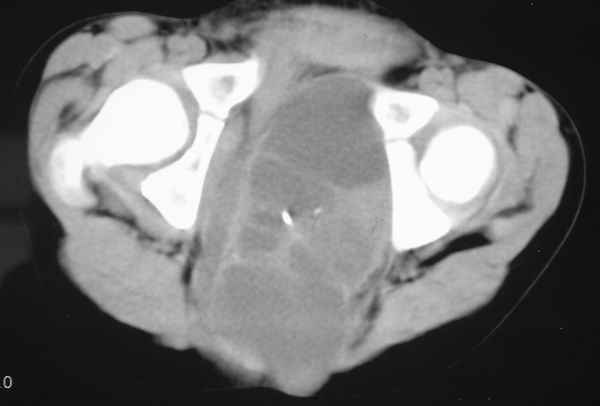

标题: PED0321:F 7 骶尾部肿瘤 有病理结果 [打印本页]

标题: PED0321:F 7 骶尾部肿瘤 有病理结果

骶尾部肿瘤 有病理结果

畸胎瘤

考虑畸胎瘤可能性大。骶尾骨无破坏。不考虑脊索瘤。

骶骨没有发现骨质破坏,畸胎瘤的可能性大